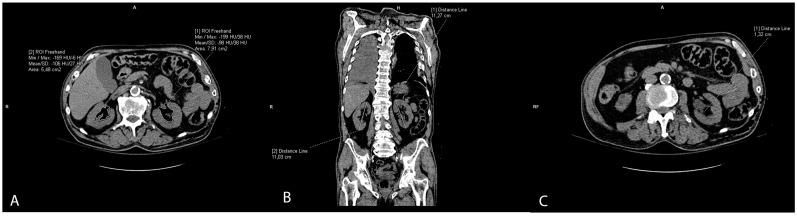

The vascular risk associated with obesity is particularly associated with visceral adiposity, but recent studies suggest that ectopic fat might contribute to the increased risk of atherosclerotic cardiovascular disease. Our study aimed to explore the connection between arterial calcification of the aorta and renal arteries with visceral and ectopic fat deposits, including liver, pancreatic, and renal sinus fat. Retrospective analysis of thoracoabdominal multi-slice computed tomography (MSCT) scans of 302 patients included measurements of calcification volumes of thoracic and abdominal aorta, and of both renal arteries. On the same scans, the visceral fat volume, liver-to-spleen ratio, pancreatic-to-spleen ratio, and both renal sinus fat areas were retrieved. Logistic regression showed the left kidney sinus fat area to be the most strongly associated with calcifications in the aorta and both renal arteries (coef. from 0.578 to 0.913, < 0.05). The visceral fat positively predicted aortic calcification (coef. = 0.462, = 0.008), and on the contrary, the pancreatic fat accumulation even showed protective effects on thoracic and abdominal aorta calcification (coef. = -0.611 and -0.761, < 0.001, respectively). The results suggest that ectopic fat locations differently impact the calcification of arteries, which should be further explored.